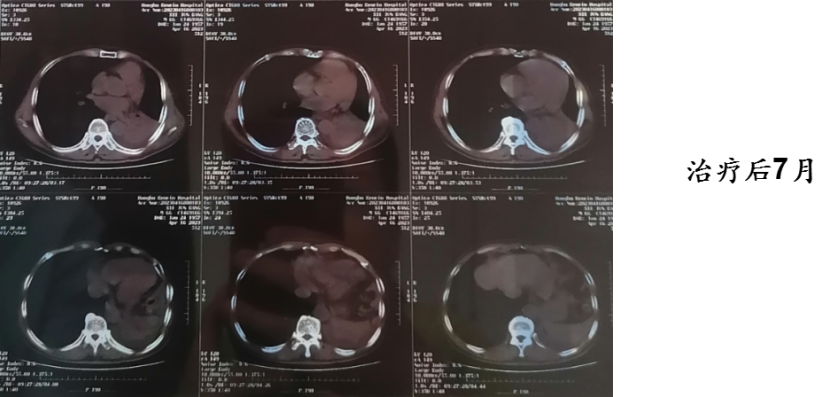

病例三:张某某,41 岁,右肺腺癌,cT3N1M0,临床分期 ⅢA,治疗9个月后病灶明显缩小。

病例提供医生:张一贺 科室:放疗中心一科(国际一部)